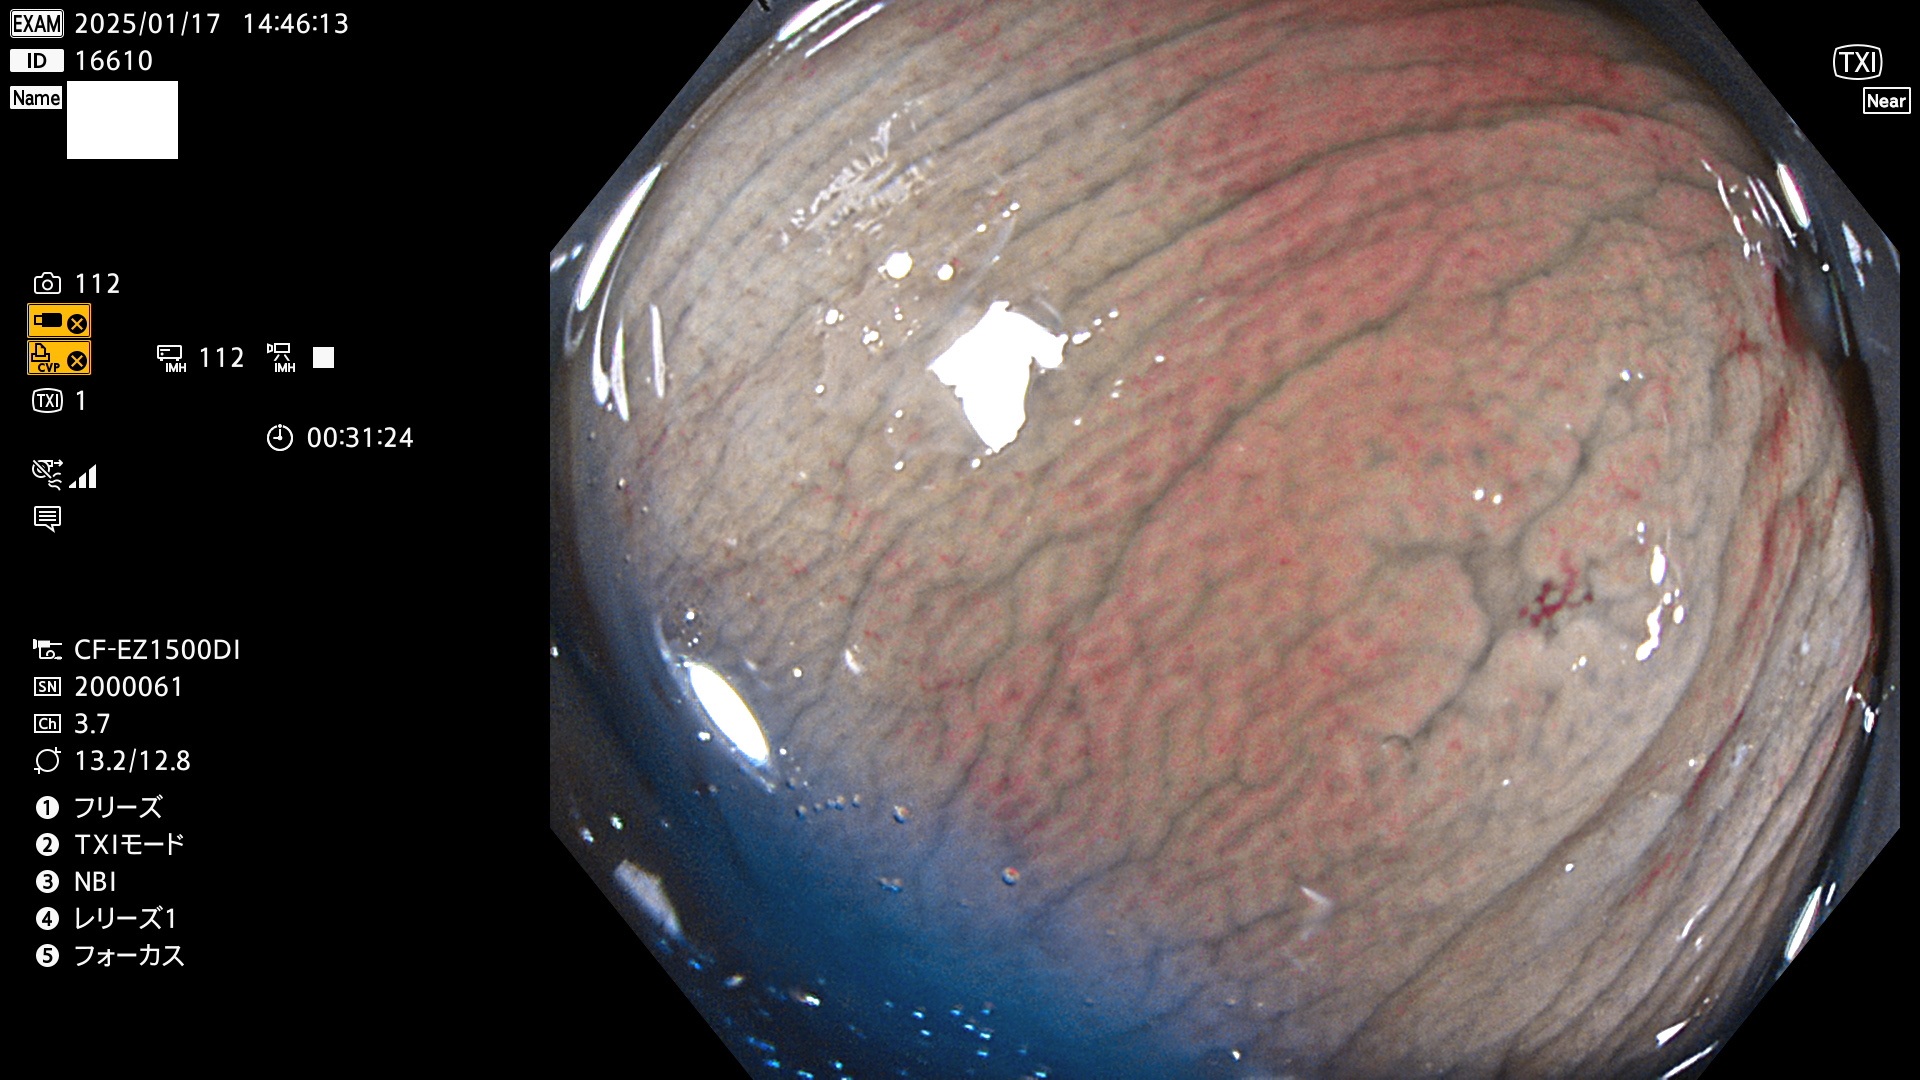

完全に平坦な物をUb、陥凹している物をUcと呼びます。最も発見が難しく危険な病変です。

毎週の検査(木・金・土・日)に発見されたUb、Uc型・腺腫を、その週の日曜の夜にUPし1週間、提示します。

抽出の対象期間 2025年1月16日〜1月19日の4日間(45件の検査)8個 (8/45=17%)